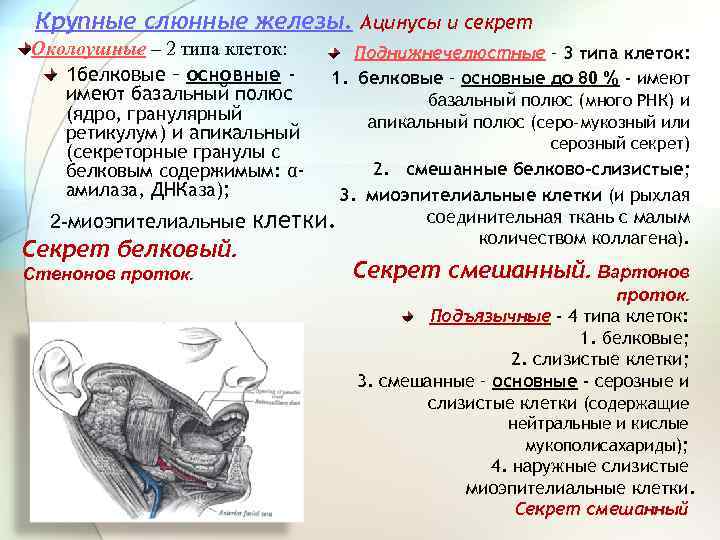

Крупные слюнные железы. Ацинусы и секрет Околоушные – 2 типа клеток: 1 белковые – основные имеют базальный полюс (ядро, гранулярный ретикулум) и апикальный (секреторные гранулы с Поднижнечелюстные – 3 типа клеток: 1. белковые – основные до 80 % - имеют базальный полюс (много РНК) и апикальный полюс (серо-мукозный или серозный секрет) 2. смешанные белково-слизистые; белковым содержимым: αамилаза, ДНКаза); 3. миоэпителиальные клетки (и рыхлая соединительная ткань с малым 2 -миоэпителиальные клетки. количеством коллагена). Секрет белковый. Стенонов проток. Секрет смешанный. Вартонов проток. Подъязычные - 4 типа клеток: 1. белковые; 2. слизистые клетки; 3. смешанные – основные - серозные и слизистые клетки (содержащие нейтральные и кислые мукополисахариды); 4. наружные слизистые миоэпителиальные клетки. Секрет смешанный